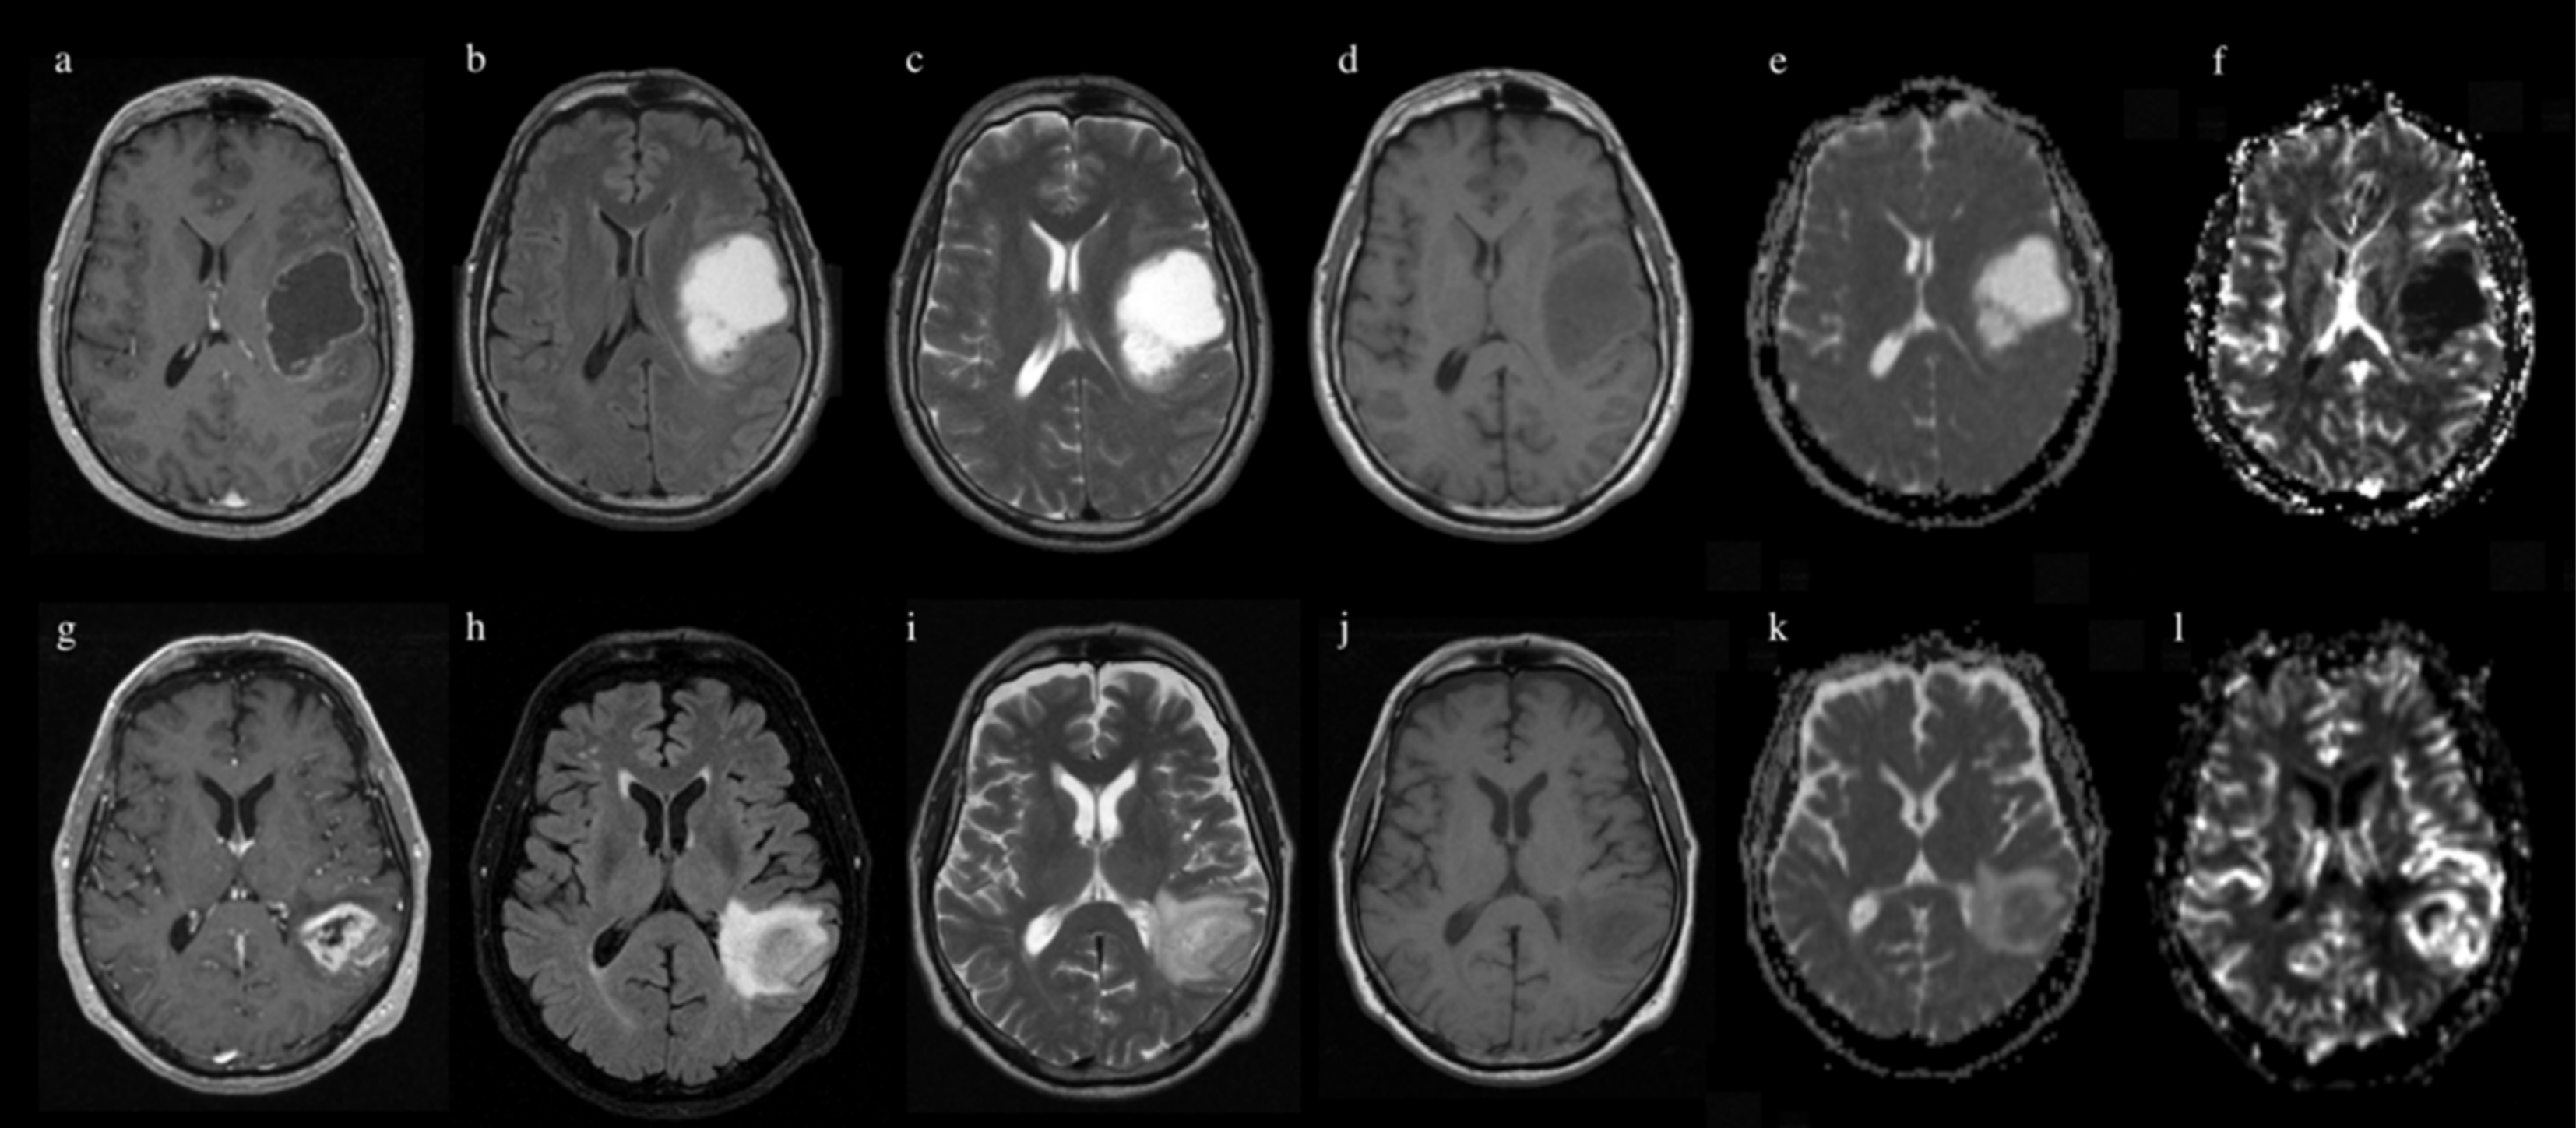

2. Materials and Methods

2.3. MR Image Acquisition

2.4. Image Processing

| Sequence | Subjects Intersection | Train/Test (Split = 0.2) | AugTrain/Test | Train:0/1 | Test:0/1 |

|---|---|---|---|---|---|

| T1 | 83 | 65/17 | 106/17 | 53/53 | 5/12 |

| T2 | 84 | 66/17 | 108/17 | 54/54 | 5/14 |

| FLAIR | 96 | 76/19 | 124/19 | 62/62 | 5/14 |

| MPRAGE | 97 | 76/20 | 128/20 | 64/64 | 5/15 |

| rCBV | 66 | 52/14 | 90/14 | 45/45 | 5/9 |

| ADC | 93 | 73/19 | 124/19 | 62/62 | 5/14 |